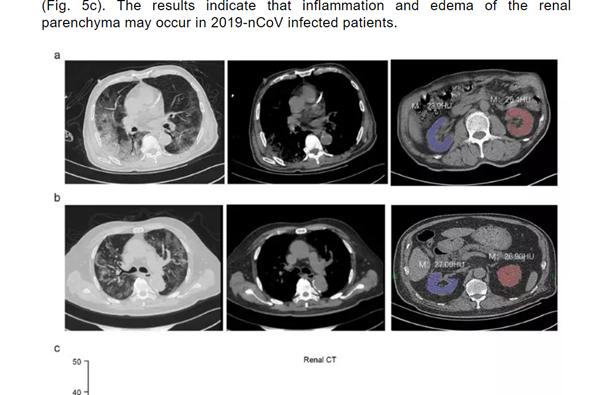

这份名为《Caution on Kidney Dysfunctions of 2019-nCoV Patients》的论文,研究了59名来源于武汉、黄石和重庆的59例感染患者病例。

结果发现, 63%的患者表现出肾功能不全的症状,CT扫描显示100%的患者肾脏影像学异常。

(图片来源:Medrxiv)